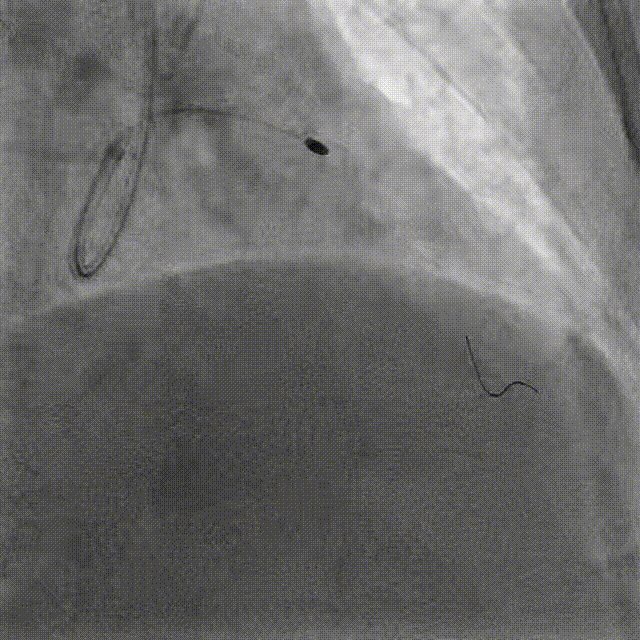

Angiography & DCB Angioplasty DCB 4.0*20mm @ 8atm, 60s

DES Deployment & Optimization DES 4.0*20mm → NC 4.0*12mm @ 20atm

Final Results